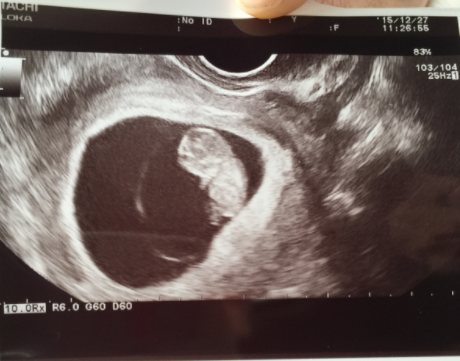

10週(10w・男の子)|ばんた さん(29歳)

エコー写真撮影時のエピソード:

五回目の妊娠で初めて30mm超え、順調と言われて感動した。 こんなに人のカタチにまでなったのも初めてだし、標準通りに成長することができてほんとよかった。

今は22週になり、順調に元気に育っており、胎動も感じられてこのまま無事産まれる事を祈ってます。